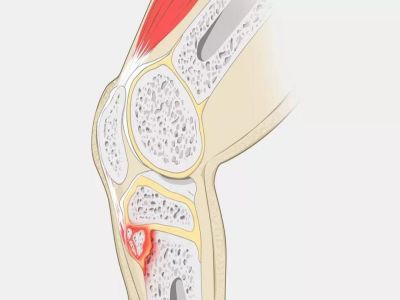

腘窝囊肿

腘窝囊肿,大多属于一种良性的关节内囊性肿物,囊内往往为关节液。症状主要是膝关节后方感觉疼痛和紧绷发胀,严重者也会导致膝关节的屈伸受限。现早期可以无压痛,但一般有波动感,B超、X光片可以看到在腘窝有一个类似球形的软组织阴影。腘窝囊肿一般如果没有不适症状可以不用处理,对人体没有什么危害。如果囊肿较大,已经引起不适症状往往需要进行治疗。一般分为关节穿刺抽吸和手术切除治疗,但在治疗前一定要诊断明确,如果腘窝囊肿是因为其他关节疾病引发,不论抽吸还是手术切除,都容易导致复发,所以找到引起腘窝囊肿的原发病很重要。